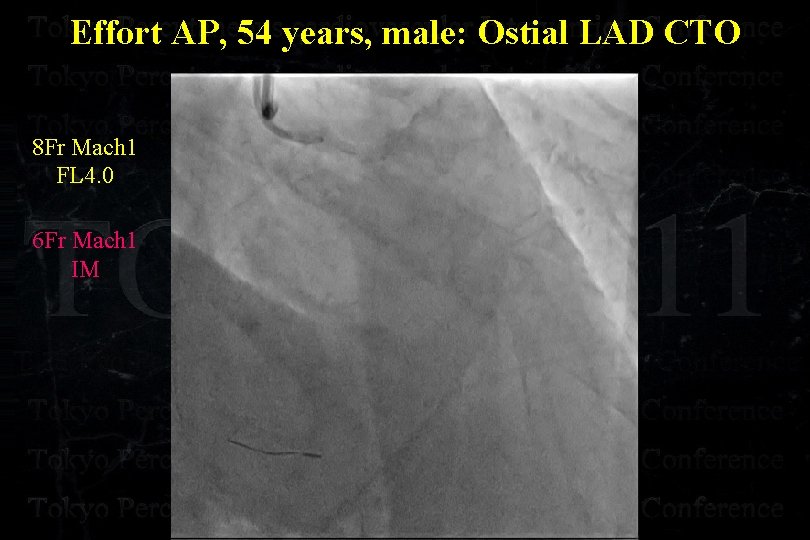

Effort AP, 54 years, male: Ostial LAD CTO

Effort AP, 54 years, male: Ostial LAD CTO

Effort AP, 54 years, male: Ostial LAD CTO

Effort AP, 54 years, male: Ostial LAD CTO

Effort AP, 54 years, male: Ostial LAD CTO

Effort AP, 54 years, male: Ostial LAD CTO

Effort AP, 54 years, male: Ostial LAD CTO Separated Conus Branch !

Effort AP, 54 years, male: Ostial LAD CTO 8 Fr Mach 1 FL 4. 0 6 Fr Mach 1 IM